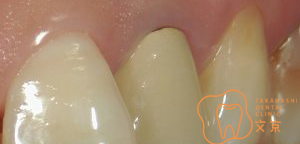

■歯の基礎となるコア 接着性能を向上させたファイバーコア

■前歯を治したい 精密審美治療・セラミックス治療

■前歯 精密審美治療

■保険の前歯を直したい

■前歯が折れてしまった、、、